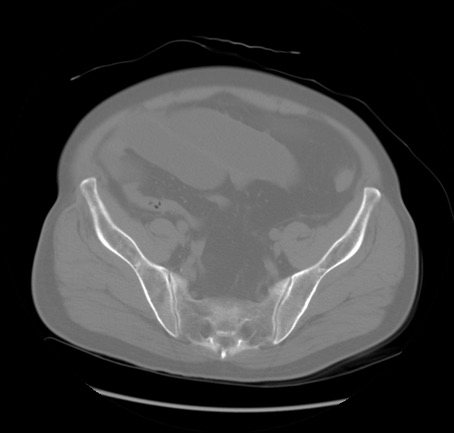

症例20(横断像)

冠状断像